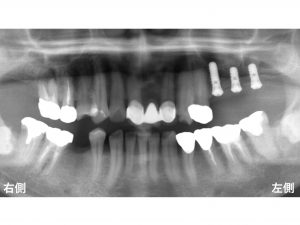

以下が初診時です。

上顎右側の奥歯に2歯欠損、

上顎左側の奥歯が3歯欠損、

下顎右側の奥歯が1歯欠損

の患者様です。